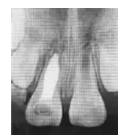

1個半月后復診,X線片示:11、21根尖孔未閉合,11根尖部Vitapex糊劑部分吸收,根中1/3內(nèi)吸收暫停,根尖周稀疏區(qū)消失,但根尖孔無閉合傾向,牙根長度無明顯變化,且略短于21的牙根長度。更換11根管內(nèi)Vitapex糊劑(圖1c)。

圖1c 術后1個半月X線片

3個月后復診,X線片示:11、21根尖孔未閉合,11根尖部糊劑無明顯吸收,雖根中1/3內(nèi)吸收未見明顯改善,但根尖孔有閉合傾向,牙根長度開始增加,牙根發(fā)育接近8期,同時發(fā)現(xiàn)11根尖閉合程度略高于21,兩者的牙根長度相近(圖1d)。

圖1d 術后3個月X線片